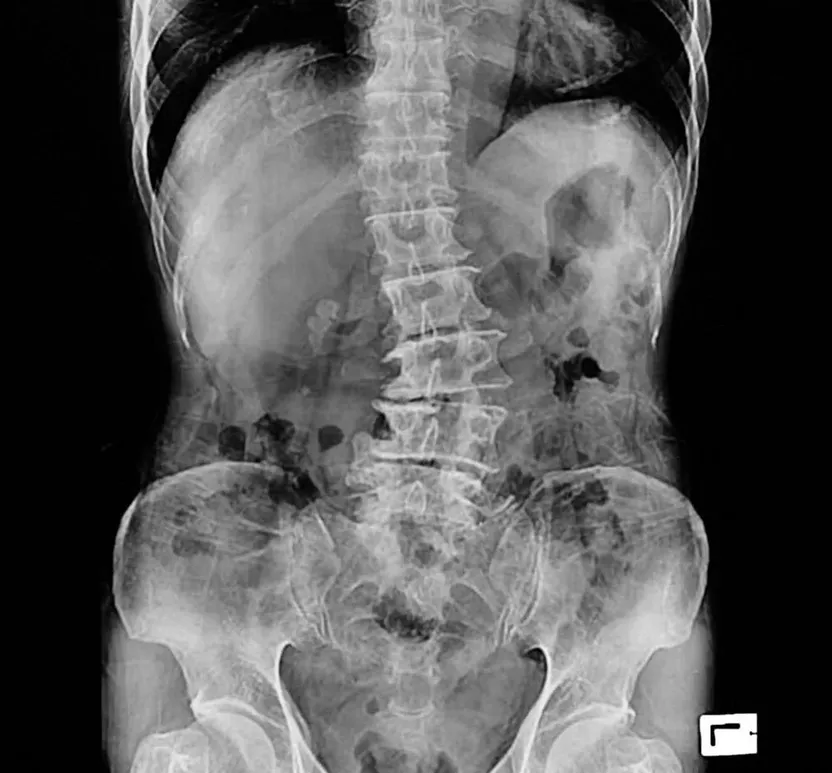

Diagnostics are very important to quality chiropractic care and x-rays are one of the most commonly used tools. Why? They are non-invasive and really give Dr. Padron a chance to see what is going on in your body so that an appropriate course of treatment can be determined. Here’s what you need to know about the use of x-rays at Happy Spine Wellness Center.

When many people think about x-rays, the image of a broken bone or sprain generally comes to mind—not spinal alignment. But many chiropractic clinics around the country use x-ray machines on a regular basis to help diagnose and treat patients.

And, when it comes to chiropractic care, seeing all the various elements of the body is not really an issue for doctors who simply want to improve a patient’s neck or back pain. All he or she really has to confirm is the layout of the bones plus any scar tissue in the body to help make a treatment decision. X-rays easily show this without fancy or expensive equipment.